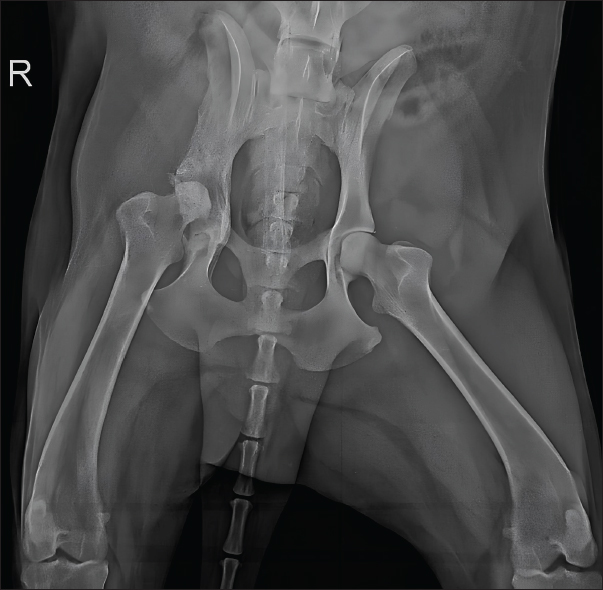

At 150 days, reevaluation included radiography and hematology, which remained within normal limits, including hepatic and renal parameters. Radiographs showed marked reduction of periosteal proliferation and osteolytic areas, primarily concentrated in the acetabular region, likely due to joint degeneration from the infection (Fig. 6).

Fig. 6. Radiographic examination of the dog 150 days after initiation of itraconazole treatment, showing marked reduction of periosteal proliferation and osteolytic areas.